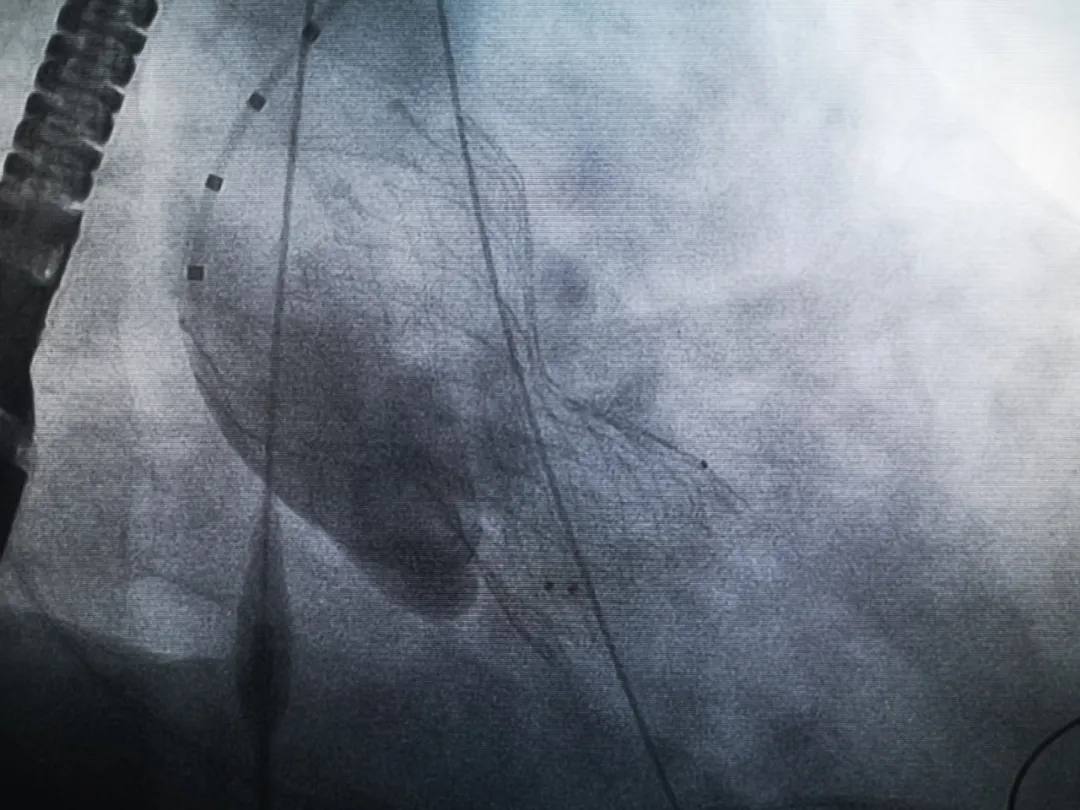

手術(shù)過程緊張而有序,心臟沒有停跳,也沒有太大的血壓波動(dòng);球囊擴(kuò)張的恰到好處,瓣膜釋放之后超聲醫(yī)生的評(píng)估是至關(guān)重要的,因?yàn)槲覀兲崆熬蜏?zhǔn)備了后擴(kuò)張,也準(zhǔn)備了瓣中瓣,甚至還準(zhǔn)備了瓣周漏封堵。所幸的是,超聲診療中心劉夢(mèng)梅醫(yī)生說:沒有返流、沒有瓣周漏,瓣膜形態(tài)良好,跨瓣壓差約17mmHg(相較于術(shù)前的87mmHg還是可以接受的)。瓣膜置入的成功并不是慶祝的時(shí)候,從戰(zhàn)場(chǎng)撤退仍然需要謹(jǐn)慎。由于王子特別胖,腹股溝區(qū)脂肪尤為肥厚,在股動(dòng)脈插管拔除、確認(rèn)搏動(dòng)正常之后,便逐層縫合。同時(shí)為了美觀、縫合之后不至于鼓個(gè)包出來,我們又仔細(xì)剪除了部分脂肪。術(shù)后次日,王子便可以下床活動(dòng)了。